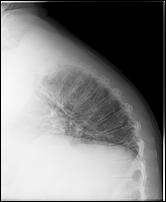

La mia ipercifosi dorsale un anno dopo

Martedì scorso sono andato a ritirare il referto delle radiografie effettuate sulla colonna cervicale e toracico-dorsale. Rispetto all'indagine precedente fatta precisamente un anno fa viene diagnosticato un incremento dell'ipercifosi dorsale. Ma le sorprese piu' grosse sembra ci siano sulla colonna cervicale. Infatti rispetto allo scorso anno viene refertata deviazione dx dell'asse verticale (lo scorso anno: somi in asse),lordosi accentuata (lo scorso anno: nei limiti la lordosi), manifestazioni spondilosiche e spondilartrosiche in C4-C6 (lo scorso anno solo spondilartrosiche). Effettivamente del peggioramento dell'ipercifosi me ne ero accorto anche io, mi sembra che addirittura ci sia stato un'ulteriore spostamento in avanti del collo e di conseguenza della testa. Il 5 luglio prossimo ho la visita fisiatrica. Purtroppo la dorsalgia non passa e sto continuando a prendere antinfiammatori tutti i giorni. ---------- Post added at 18:05:02 ---------- Previous post was at 17:01:48 ----------